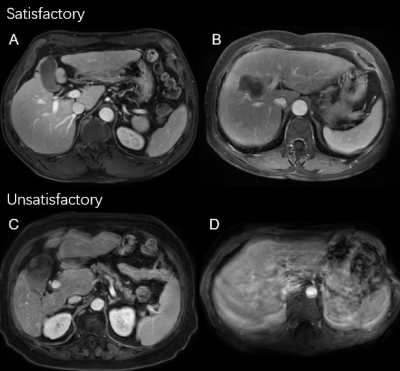

Two radiologists jointly scored the image quality of each phase of each enrolled case on an A-D scale, with A representing good and D representing poor quality (Fig. 2). We treated the image with quality A/B as satisfactory, and C/D as unsatisfactory.

Fig.2 Example of binarized image quality scores. A = excellent, B = good, C = unsatisfactory, and D = poor image qualities, respectively.